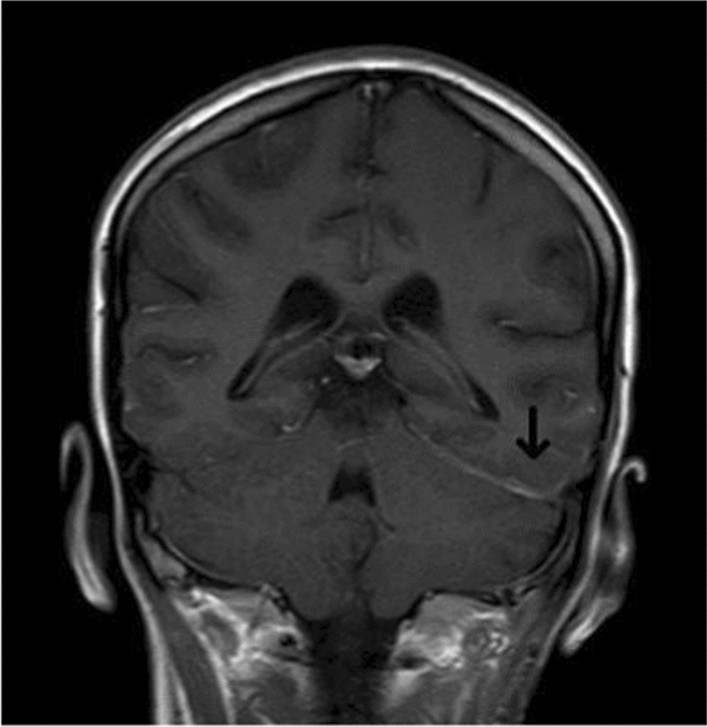

Mark, 58, was told in 2015 that his EGFRmutated nonsmallcell lung cancer had spread to his liver and brain. He started osimertinib, a thirdgeneration targeted drug, and added stereotactic radiation for the brain lesions. Fast forward to 2025Mark is still on therapy, working parttime, and hiking with his grandchildren every summer. His secret? Staying active, adhering strictly to medication, and leaning on a local support group.